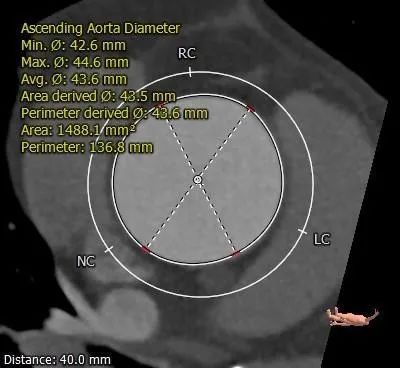

术前CT评估:

根部测量:

Type 0 型二叶瓣,重度钙化,两窦对合边缘附近钙化,左窦内可见明显钙化团块,瓣膜锚定难度适中,瓣膜植入受钙化及二叶瓣瓣口形态影响存在少量偏多

瓣周漏风险,瓣膜移位风险增高

冠脉开口高度可,未见冗长瓣叶,结合瓦氏窦、STJ内径综合预估,冠脉风险低

推荐20mm球囊预扩,预装AV23瓣膜,推荐瓣环下零位释放